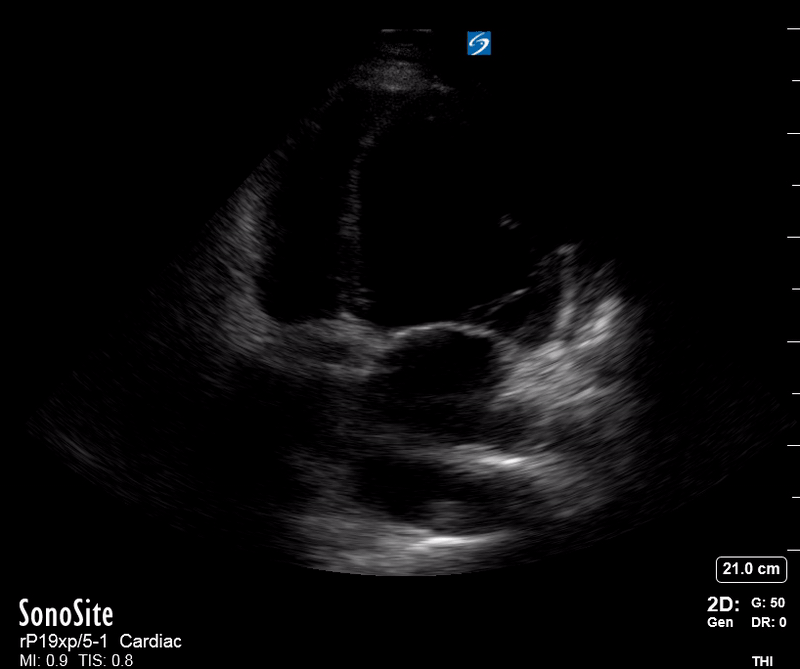

The PLAX view is versatile and allows the recognition of multiple landmarks, making it good for visual estimation of LV contractility. It is essential to optimize the view ensuring a true sagittal long axis, as being oblique to the LV chamber may underestimate its size and overestimate its emptying. The PSAX view at the level of the papillary muscles reveals the entire muscular circumference and concentric squeeze of the LV. It is useful to estimate both global function and focal wall motion abnormalities. The A4C view, although technically challenging, provides good insight into the global myocardial function and chamber size.

LV CONTRACTILITY

Qualitative assessment of the LV and visual estimation of Ejection Fraction is based on three parameters:

Endocardial excursion.

Myocardial thickening.

Movement of the anterior leaflet of the mitral valve.

A qualitative assessment is typically categorised as:

Normal (LVEF 50-65%)

Moderately Depressed (LVEF 30-50%)

Severely Depressed (LVEF < 30%)

Hyperdynamic (LVEF > 65%)

SIGNIFICANTLY IMPAIRED / DILATED LV

A severely depressed LV contractility, particularly when paired with a plethoric IVC or lung B-lines, indicates systolic heart failure. Chronically raised afterload can lead to severe dilation of the LV.